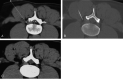

F<sc>ig</sc> 2.

Fig 2.

Infiltration of the gas mixture. A, L4-L5 right intraextraforaminal disk herniation (arrows). B, Correct positioning of the needle. C, Distribution of the gas mixture in the herniation (arrowheads) and in the facet joint (arrows).